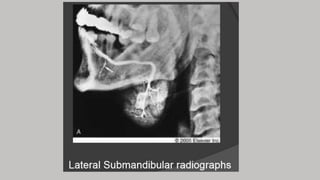

Filming of SM

Inferior superior

-Elevate the patient's thorax on

several firm pillows.

- Place the film in the mouth with the

long axis directed transversely.

- Central ray perpendicular to the

plane of the film

Contd..

• Center the IR to the inferior margin

of the angle of the mandible.

• Adjust the patient's head in a true

lateral position

• depressing the floor of the mouth

to displace the submandibular

gland below the mandible

• Neck should be hyper extended so

that the submandibular gland is

projected below the mandible